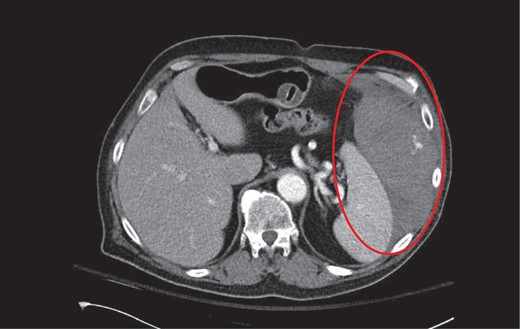

CT axial with intravenous contrast demonstrating a large left abdominal wall hematoma with active contrast extravasation from an intercostal artery.